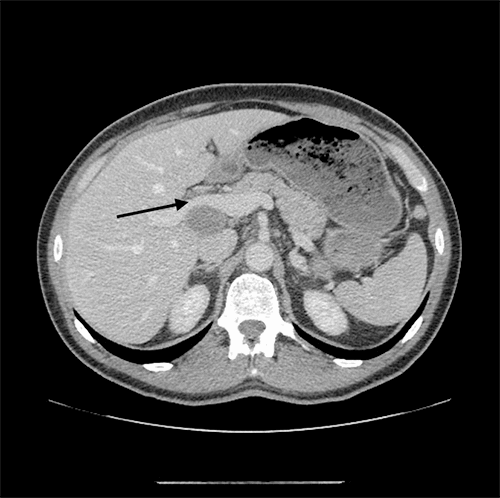

Pathology suggested a poorly differentiated NEC with a Ki-67 >80 percent. The patient self-referred to our institute, where he underwent a repeat ERCP and EUS guided biopsy of the portal lymph nodes. Interestingly, ERCP demonstrated fibrinous exudative material in the CBD causing obstruction, which resembled the same material aspirated from the portal lymph node. A plastic stent was deployed for biliary decompression. Pathology results were suggestive of, but indeterminate, for NEC. The patient’s chromogranin A was normal at 72. Serotonin and 5-HIAA levels were negative. Given the diagnostic uncertainty and the patient’s ongoing abdominal pain, the decision was made to proceed with a laparoscopic cholecystectomy and CBD exploration. The gallbladder was found to be severely inflamed, with an obvious intra-luminal mass, and was removed with a portion of segment 5 to avoid bile spillage (see Figure 3 and Figure 4). Final pathology results confirmed a poorly differentiated NEC with a Ki-67 >50 percent.

Figure 4: Patient’s gallbladder opened to reveal 10 x 5.5 x 4 cm mass